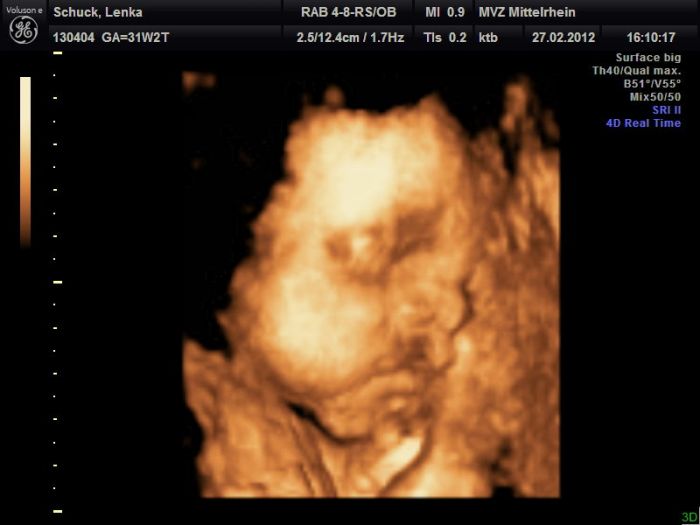

Veru: taky to máme po tatínkovi... Už na 3D v 7. měsíci to bylo vidět :D